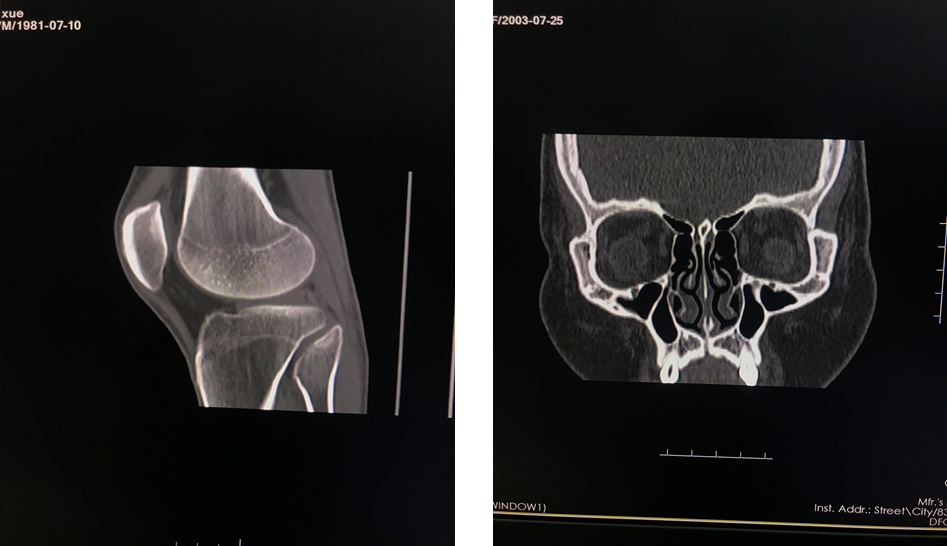

四、开展项目:科室现常规开展全身各部位CT平扫及增强检查、CT三维重建、CT血管造影(CTA、CTV)、(包括冠状动脉CTA)、CT尿路造影(CTU)、全身各部位DR摄片检查、床边摄片、同时开展胆系T管造影、CT定位下穿刺活检。

全身部位三维重建

全身骨三维重建